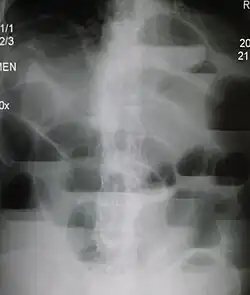

W przeglądowym zdjęciu RTG jamy brzusznej w pozycji stojącej lub bocznej widoczne są poziomy płynu w rozdętych pętlach jelitowych, co jest efektem rozdzielenia treści jelitowej na frakcję gazową i płynną. Poziomy płynów o długości przekraczającej 2,5 cm są uważane za patognomiczne dla niedrożności jelit[9]. W niedrożności mechanicznej z zatkania rozdęcie pętli pojawia się powyżej miejsca zatkania. W niskiej niedrożności rozdęte pętle nakładają się na siebie utrudniając rozpoznanie. W niedrożności zlokalizowanej w jelicie grubym i wydolnej zastawce krętniczej-kątniczej rozdęte jest tylko jelito grube[18].

Niedrożność z zadzierzgnięcia daje podobny obraz, rzadziej pojawia się obraz pseudoguza lub pętla z poziomem płynu i gazu z nakłądającymi się na siebie ścianami (obraz "ziarna kawy"). W niedrożności porażennej poziomy płynów są mniej liczne i występują na całej długości jelita[18].